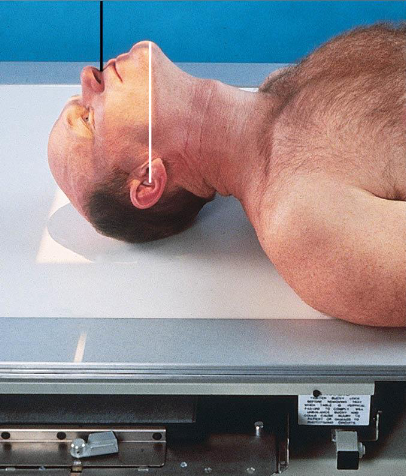

Acanthioparietal (Reverse Waters) facial bones

patient position:

supine

MSP centered to midline

part position:

extend chin and neck so OML forms a 37 degree angle with the IR plane

MML almost perpendicular

MSP perpendicular to IR

respiration suspended

CR:

perpendicular, enters acanthion

collimation:

1 inch beyond the lateral sides of the face, superiorly just to the skin shadow, and inferiorly to the chin

no larger than 8 ×10 inches